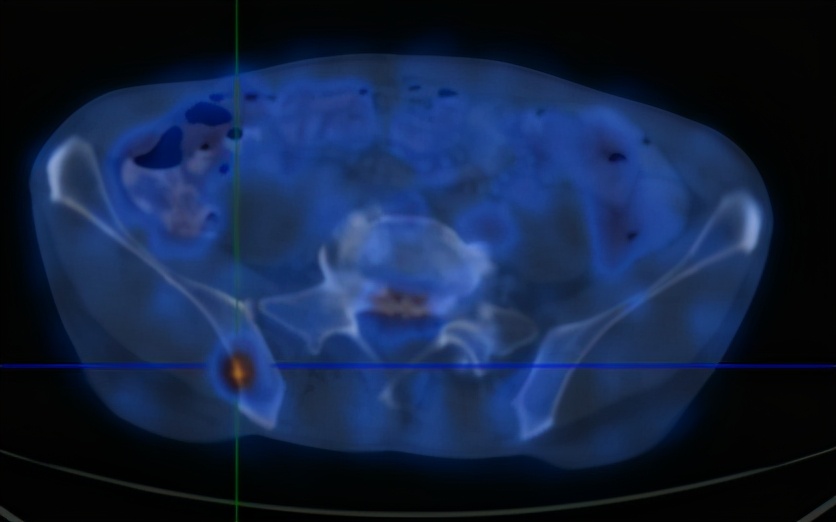

2020-6-19患者行全身PET/CT示:

1、左下肺前内基底段支气管开口处结节,糖代谢增高,考虑中央型肺癌并远端阻塞性炎症、不张;全身(双侧颈部、双侧锁骨上下窝、两侧肺门、纵隔、贲门旁、胰头后方、腹主动脉旁及双侧髂血管旁)多发淋巴结转移;双肺多发转移;肝S4及S5转移;胰头部结节转移;全身多发骨转移;综上,建议活检除外结核。

2、甲状腺双侧叶多发结节,糖代谢增高,不除外恶性肿瘤,建议追踪。左侧肾上腺稍增粗,糖代谢轻度增高,建议追踪。

3、前列腺钙化灶。右侧阴囊钙化灶。

4、心包少许积液。